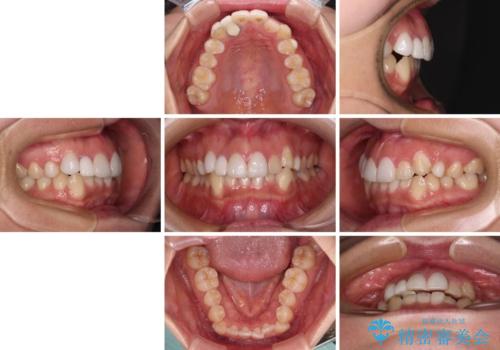

- 上下前歯のデコボコを気にして来院された患者様です。

インビザラインによる上下歯列の拡大と、IPR(歯と歯の間を削る)にるスペースの獲得により、前歯のデコボコを改善することとしました。